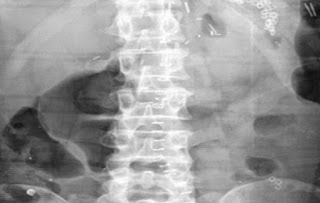

ΑΠΙΣΤΕΥΤΗ υπόθεση -Η ακτινογραφία που πάγωσε γιατρούς και αστυνομικούς της Κρήτης – Ο κρατούμενος έλεγε την αλήθεια (φωτο)

Λίγο έλειψε να στοιχίσει τη ζωή στον 30χρονο

Το πρωί του Σαββάτου ζήτησε και είδε το διευθυντή των φυλακών, στον οποίο είπε ότι έχει καταπιεί ένα ρολόι χειρός (χωρίς το μπρασελέ).

Ο 30χρονος διεκομίσθη στο Βενιζέλειο νοσοκομείο όπου υποβλήθηκε σε γαστροσκόπηση και οι γιατροί εντόπισαν και αφαίρεσαν από το στομάχι του το ρολόι! Ακόμα δεν έχουν αποσαφηνιστεί οι συνθήκες κάτω από τις οποίες κατιάπιε το ρολόι, κάτι που αναμένεται να γίνει τις επόμενες μέρες, όταν ο νεαρός επιστρέψει στις φυλακές…

Σύμφωνα πάντως με δελτίο τηλεοπτικού σταθμού , ο κρατούμενος κατάπιε το αντικείμενο γιατί ήθελε να πάρει άδεια.